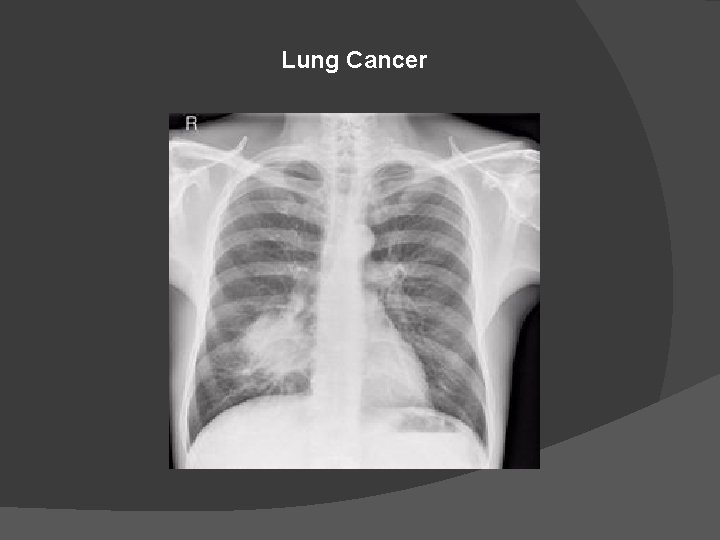

Lung Cancer